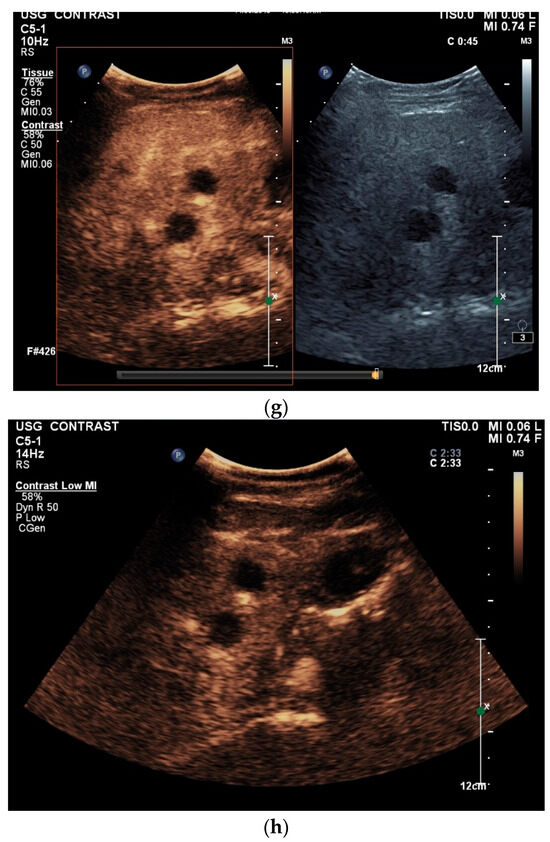

Figure 2.

A case of extrapulmonary tuberculosis: 33 y/o male from a country at high risk of tuberculosis. Thoracic pain and fever led to a suspicion of pericarditis. There was no pericardial effusion. There were no pulmonary infiltrations or pleural effusions in the chest CT, but there were enlarged mediastinal lymph nodes. Ultrasound and CT also showed subdiaphragmal enlarged lymph nodes and small nodular splenic changes. The diagnosis was confirmed using the transgastric EUS-guided biopsy (19 G Olympus) of the lymph nodes in the hepatic hilum. Enlarged lymph nodes in the hepatic hilum (a); adjacent to the pancreatic head (b); transabdominal ultrasound (TUS) using a linear transducer of 9 MHz. The hypoechoic central parts are conspicuous (a,b). Rounded lymph nodes are observed as being peripancreatic (c) and as being in close proximity to the gallbladder wall (d). The lymph nodes are visualized between the markers. In the EUS, paragastric lymph nodes are enlarged, rounded, very hypoechoic, with hypoechoic central parts, and forming conglomerates. A central vascular hilum cannot be delineated in the CDI (e). The hypoechoic central parts are softer during elastography (f). EUS also shows enlarged hypoechoic lymph nodes in the hepatic hilus, with hypoechoic central parts that lack a central vascular hilum (g). Elastographically, the lymph nodes are indifferent (h). The diagnosis is confirmed using EUS-guided biopsy (i) with evidence of granulomatous inflammation, caseous necrosis, detection of acid-fast rods, and Mycobacterium tuberculosis in the PCR. In the spleen, single hypoechoic lesions < 5 mm are visible during transabdominal ultrasound using a linear transducer of 9 MHz. Otherwise, fine-grained hypoechoic lesions can only be guessed at (j). With magnification using a 9 MHz transducer, multiple hypoechoic lesions < 3 mm can be delineated (k). These do not reveal any vessels in the Power Doppler (l). EUS confirms multiple hypoechoic splenic lesions, in line with splenic tuberculosis (m).